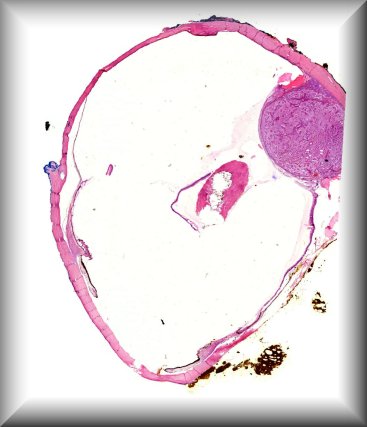

Steffen Heegaard (Copenhagen): Haemolacria in a 72-year-old man. Protocol |